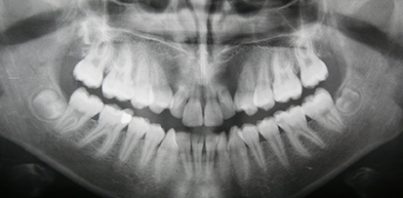

Regular six-month check-ups will include a thorough exam and x-ray, oral cancer screening, cleaning and removing tartar and plaque, polishing, fluoride treatments and sealants to protect your teeth from cavities.

Regular check-ups are important for this very reason. We want to be able to detect problem areas as soon as possible to prevent further decay or infection. We’ll help you reverse the issue and provide you with a thorough oral hygiene routine to stick too.